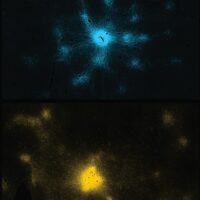

Understanding the Neural and Metabolic Factors Behind Fluid Intelligence

Examining how the distribution of neural energy production and efficiency in the frontal and parietal lobes relate to fluid intelligence.